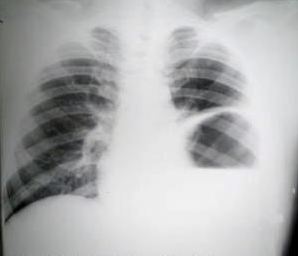

Radiología del tórax:

Sonda nasogastrica con contraste

Evidencia el fundus gastrico en la base del hemi tórax izquierdo, (contraste digestivo y la sonda llena de contenido radiopaco), unión cardioesofagica in situ, anillo o brecha diafragmática, borramiento del seno costo diafragmático  y borramiento de la linea diafragmática Izquierda, se confirma la presencia de hernia diafragmática Izquierda.